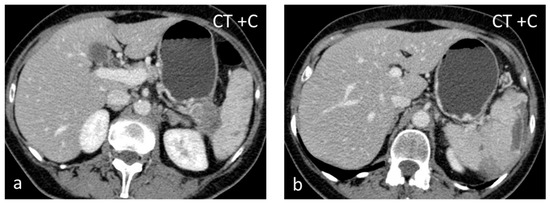

Splenic infarct can be of either arterial or venous origin. Global infarction may be caused by occlusion of the splenic artery. Occlusion of a segmental artery leads to infarction if non-communicating branches are affected. Obstruction can be caused by cardiac emboli or local thrombosis, facilitated by systemic disorders such as vasculitides, hematologic disorders (e.g., sickle cell anemia), leukemia, or lymphoma. There is a great diversity of mechanisms and etiologies for splenic infarction, but it is a rare event with a reported incidence of only 0.016% of admissions to an academic general hospital over 10 years [31]. Acute splenic infarcts usually appear on US as wedge-shaped, peripheral hypoechoic lesions pointing toward the splenic hilum. Over time they become hyperechoic, simulating a pseudolesion; the lack of vascularity at color-Doppler aids in the differential diagnosis. On non-contrast CT, the detection of infarcts is difficult, while after intravenous contrast administration, they typically appear as peripheral, wedge-shaped defects (Figure 5). In the case of global infarction, peripheral contrast enhancement due to collateral flow from capsular vessels can be seen (“rim sign”) [31]. The SI on T1-WI depends on the age of the lesion.

Figure 5.

Splenic infarct. Axial CECT images (a,b) demonstrating peripheral hypoperfused area.